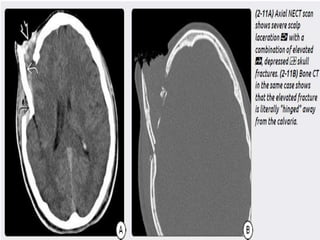

 Scalp injury –

1) laceration-Focal discontinuity, soft tissue

swelling, and subcutaneous air are commonly

b) Depressed Skull Fractures- Depressed skull

fractures typically tear the underlying dura and

arachnoid and are associated with cortical

contusions and potential leakage of CSF into

the subdural space. Fractures extending to a

dural sinus or the jugular bulb are associated

with venous sinus thrombosis in 40% of cases.

c) Elevated Skull Fractures- uncommon, often

combined with depressed fracture. Knife

penetration.